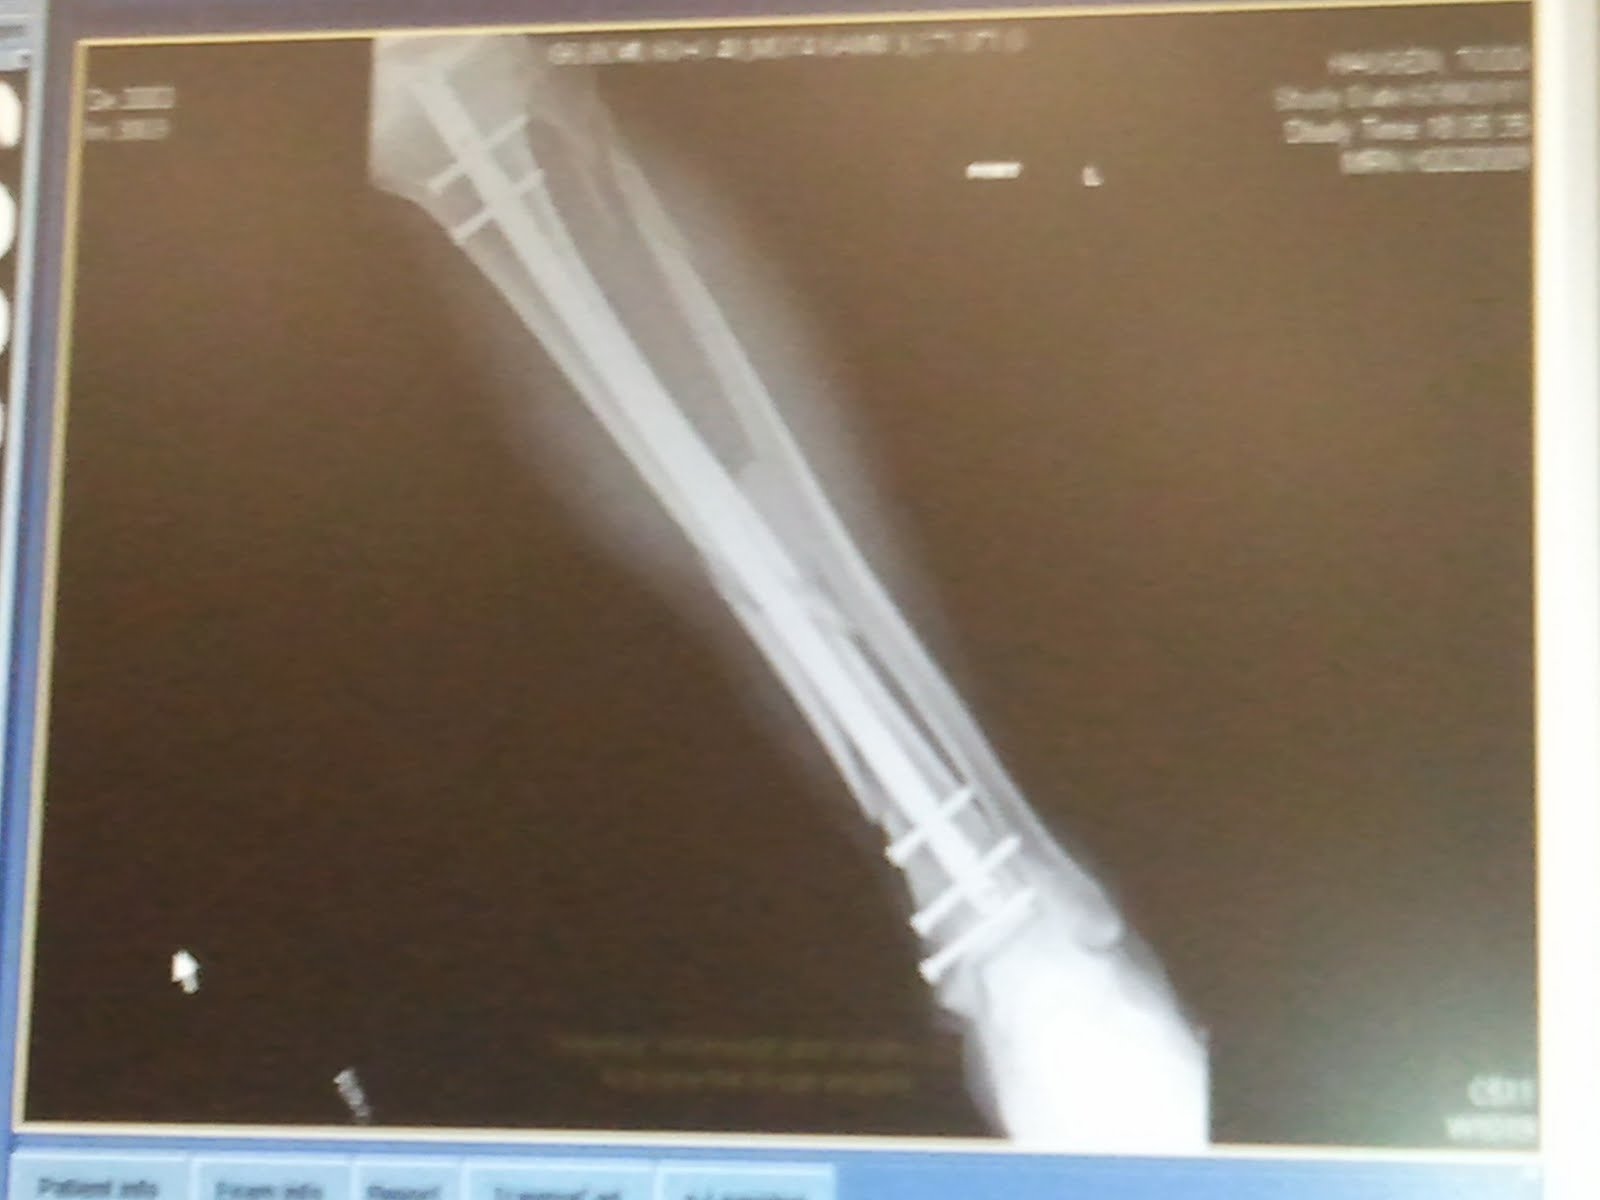

I am not sure what kind of pecking order surgeons have but clearly there is one and my Dr was higher on the order than I was, sad considering I was the patient. Regardless I learned that having an Orthopedic Dr on speed dial is a good idea if you are a skier! Here is what my leg looks like today, yep still attached!